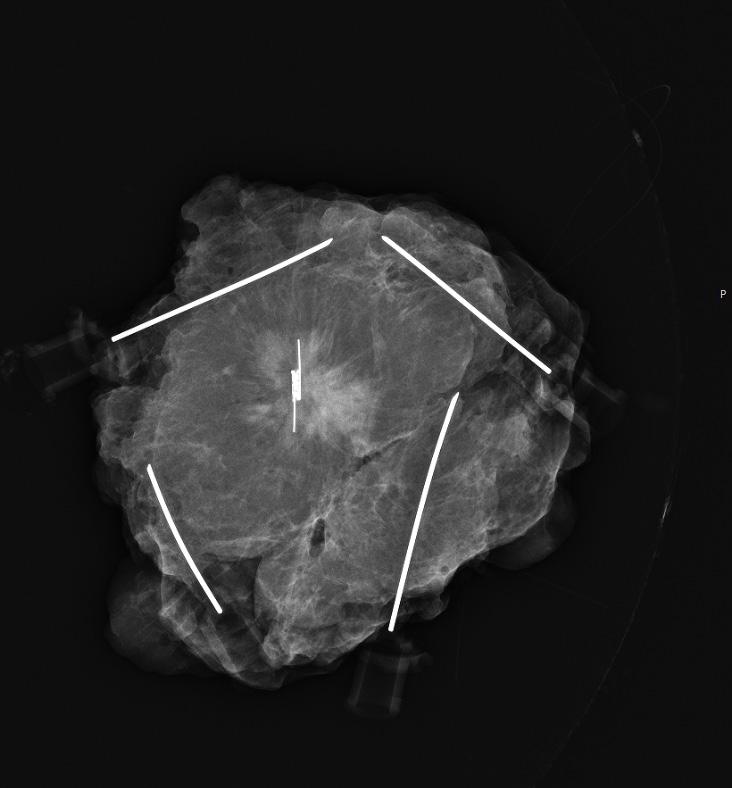

FIGUR 4: Rekonstruksjon med LICAP. 44 mm kalk i nedre laterale kvadrant, biopsert cancer mammae og DCIS grad 3. A) Preoperative bilder. To merketråder er lagt perkutant for å avgrense eksisjonsområde nedad lateralt. Fremre aksillærlinje er påtegnet og brystets omslagsfold oppad og antatt eksisjonsområde er markert med stiplede linjer. LICAP-lapp påtegnet ut lateralt i forlengelsen av intramammær fold. Kryss markerer utdopplede perforanter, pålitelige og typisk beliggende i 5.-8. interkostalrom i “triangle of plenty”. B) Perioperative bilder. Hele nedre laterale kvadrant er tømt og vaktpost lymfeknute er fjernet. Lappen er deepitelialisert, løsnet med bevarte intercostalperforanter, og roteres deretter inn i tumordefekten. Man tilstreber å overfylle defekten ettersom strålebehandling normalt vil krympe lappen. C) Kontroll 9. postoperative dag. Normal postoperativ hevelse. Bevart form. Blåfarge ses i hud etter SN-prosedyre. Bilder publisert med pasientens skriftlige samtykke.

Volumerstatning: For kvinner med små til middels store bryst (100-700 mL) eller bryst uten ptose kan det være vanskelig å lukke en stor vevsdefekt etter tumorreseksjon. For å opprettholde form og volum i brystet benytter man ofte volumerstatning med lokale lapper av deepitelialisert hud og subkutant fettvev. Interkostale kar mellom hvert ribben avgir perforerende grener til subkutant vev på brystkassen. Eksempler på slike brystveggsperforatorlapper er LICAP, MICAP and AICAP (lateral,

medial og anterior intercostal artery perforators). MICAP og AICAP høstes fra inframammærfolden og brukes ofte for reseksjoner medialt i brystet. Mest benyttet er LICAP, som høstes fra laterale thoraksvegg, og kan gi betydelig volum, spesielt lateralt (Figur 3). Incisjonen vil skjules av en brystholder, da den legges i folden under brystet og lateralt på brystkassen. Ved store defekter i øvre og mediale del av brystet eller behov for å erstatte hele brystkjertelen kan LTAP (lateral thoracic artery perforator) eller TDAP (thoracodorsal artery perforator) være alternativer (10, 13, 16).